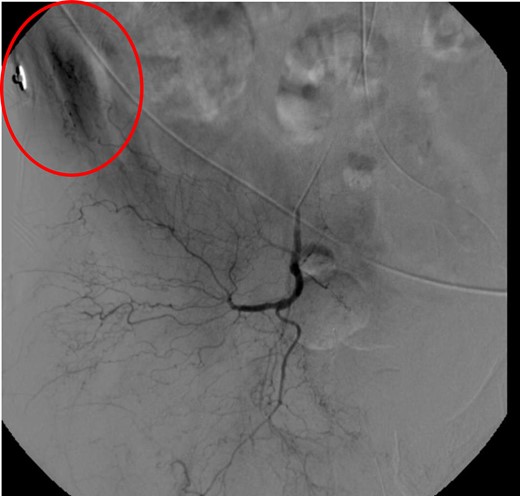

CT abdomen/pelvis with contrast was performed and a blush of contrast was noted posterior to the right pubic bone. Prior to taking patient for exploratory surgery, he was transferred to the interventional radiology suite where a pelvic angiogram was performed revealing an abnormal blush localized to the distal branches of the right iliolumbar artery (Fig. 2). Delayed phase of the angiogram demonstrated early venous filling consistent with a traumatic arteriovenous fistula which was embolized with 300–500 µ of embospheres and three 3 × 2 microcoils (Figs 3 and 4).

CT angiogram delayed phase of angiogram shows early venous filling consistent with AV fistula.